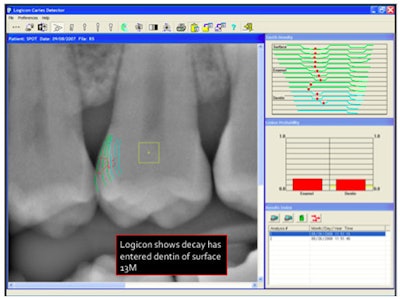

The Logicon software analyzes the lesion.

![]() |